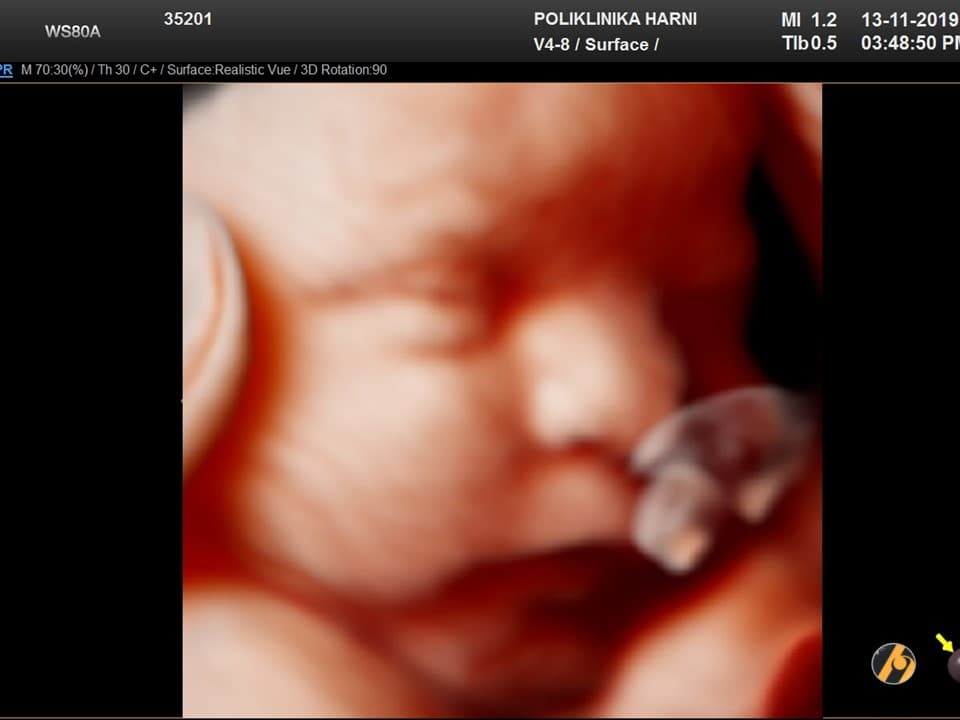

Vaša beba dugačka je oko 44 cm, a teška 2,300 – 2,550 g.

beba